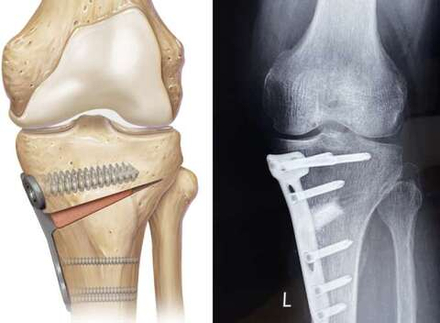

Артроскопические операции коленного сустава

Артроскопическое вмешательство показано при серьезных травмах коленного сустава, когда выявляются повреждения внутрисуставных структур:

• разрывы и надрывы менисков

• повреждения крестообразных связок

• патологии синовиальной оболочки

• повреждения суставного хряща

Артроскопия позволяет восстановить целостность структур коленного сустава без вскрытия суставной полости и с минимальной травматизацией мягких тканей.